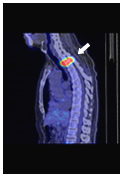

身体の形態も

病変も一目瞭然

病変は見えているが

身体の形態はぼやけている

PET-CT検査は、がん細胞の成長・増殖・転移や治療効果を知るための有効で的確な検査法です。病巣の有無を調べるためPET(陽電子放出断層撮影)と、病巣場所を確認するためのCT(コンピュータ断層撮影)による2つの画像を同時に撮影することで、がんの有無と位置・転移場所・大きさを、一回の全身撮影で診断できます。